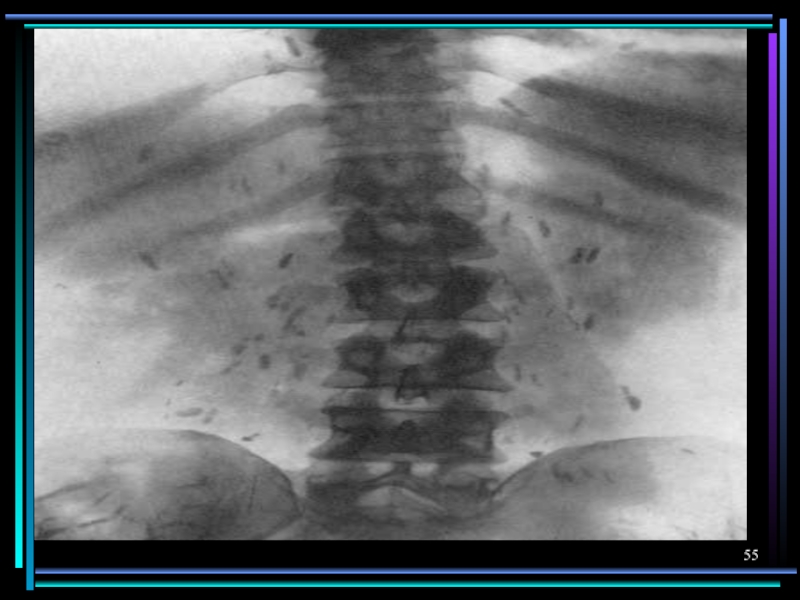

Слайд 52Поражение опорно–двигательного аппарата

Трихинеллез

Эхинококкоз

Цистицеркоз

Ангиомиозит скелетных мышц: резкие боли при движении, отек и

болезнен-ность при пальпации, ч/з 5 недель инкапсуляция личинок, ч/з несколько месяцев – начало обызвествления

2-3% кист локализуются в костях с развитием многочисленных пузырей в костном канале с асептическим некро-зом кости. Характерны спонтанные переломы без предшествующей боли. Вторично поражаются суставы.

Цистицерки локализуются в мышцах плечевого пояса и бедра. Не пальпиру-ются, боль отсутствует, ч/з несколько лет обызвествляются. Видны на R-грамме – до 1см.